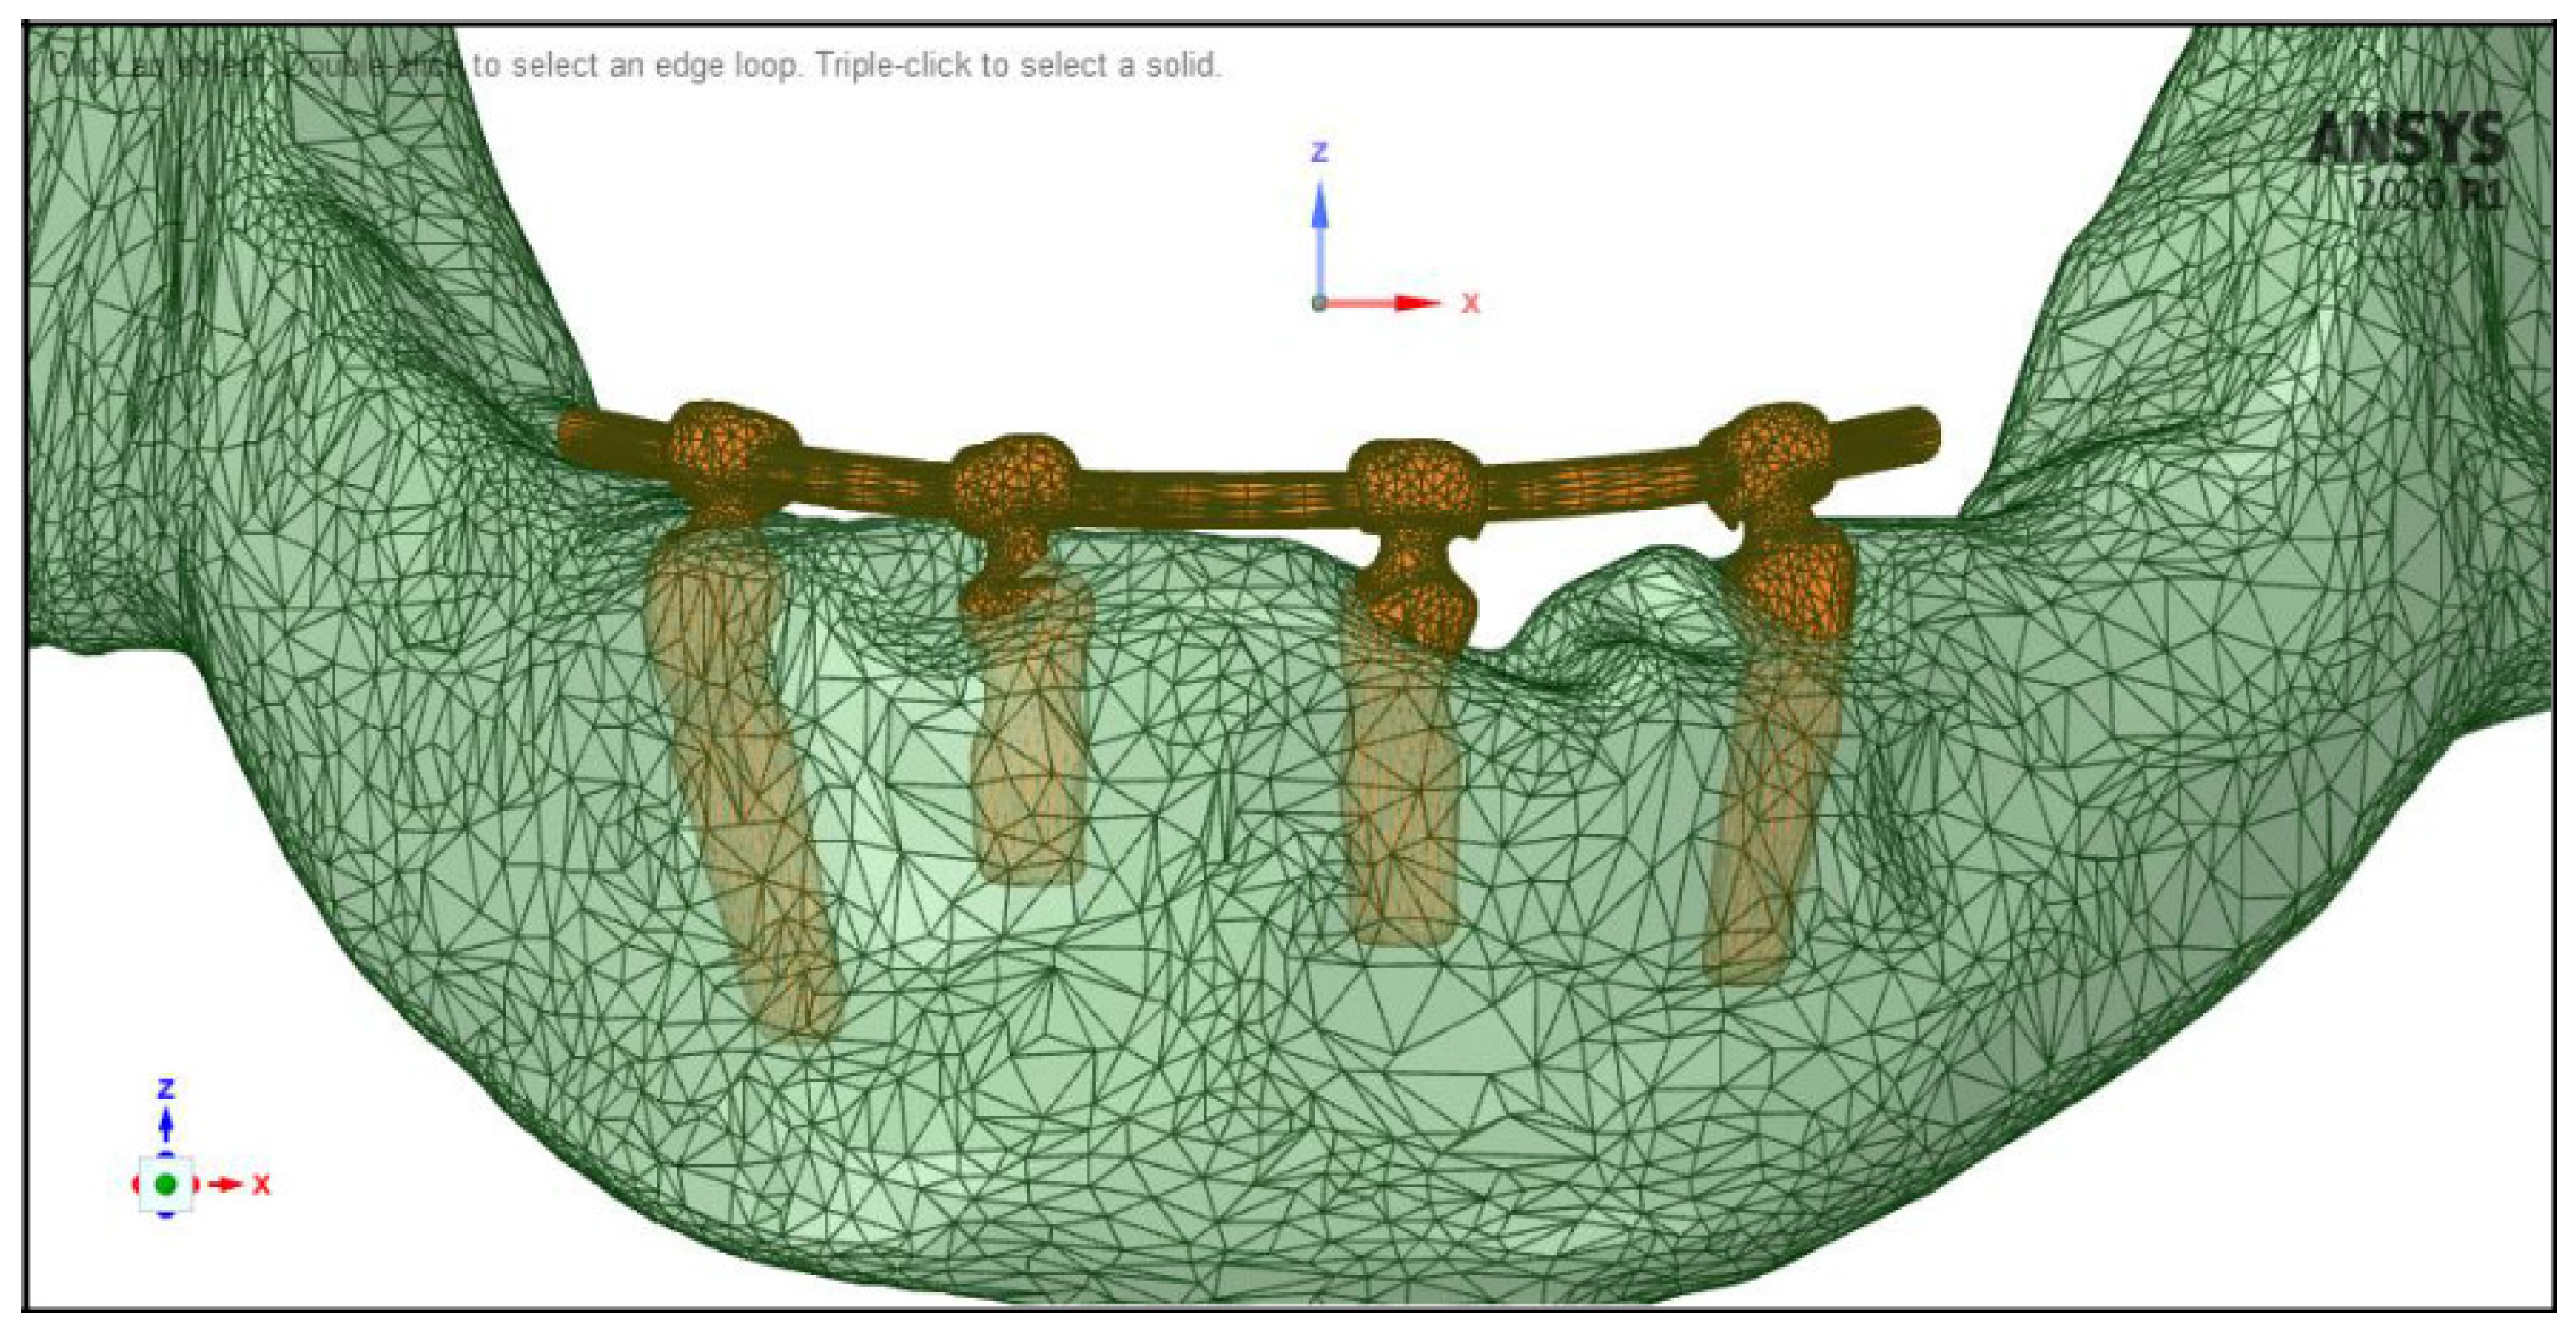

2.4. Meshing, Boundary Conditions